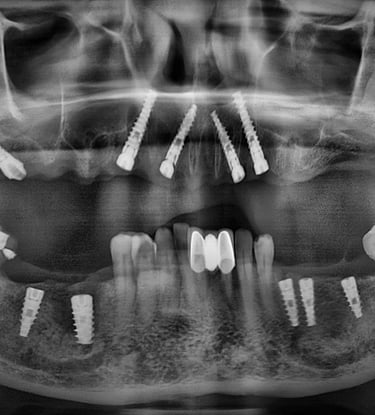

Multiple Tooth Implants

Full Mouth Implants